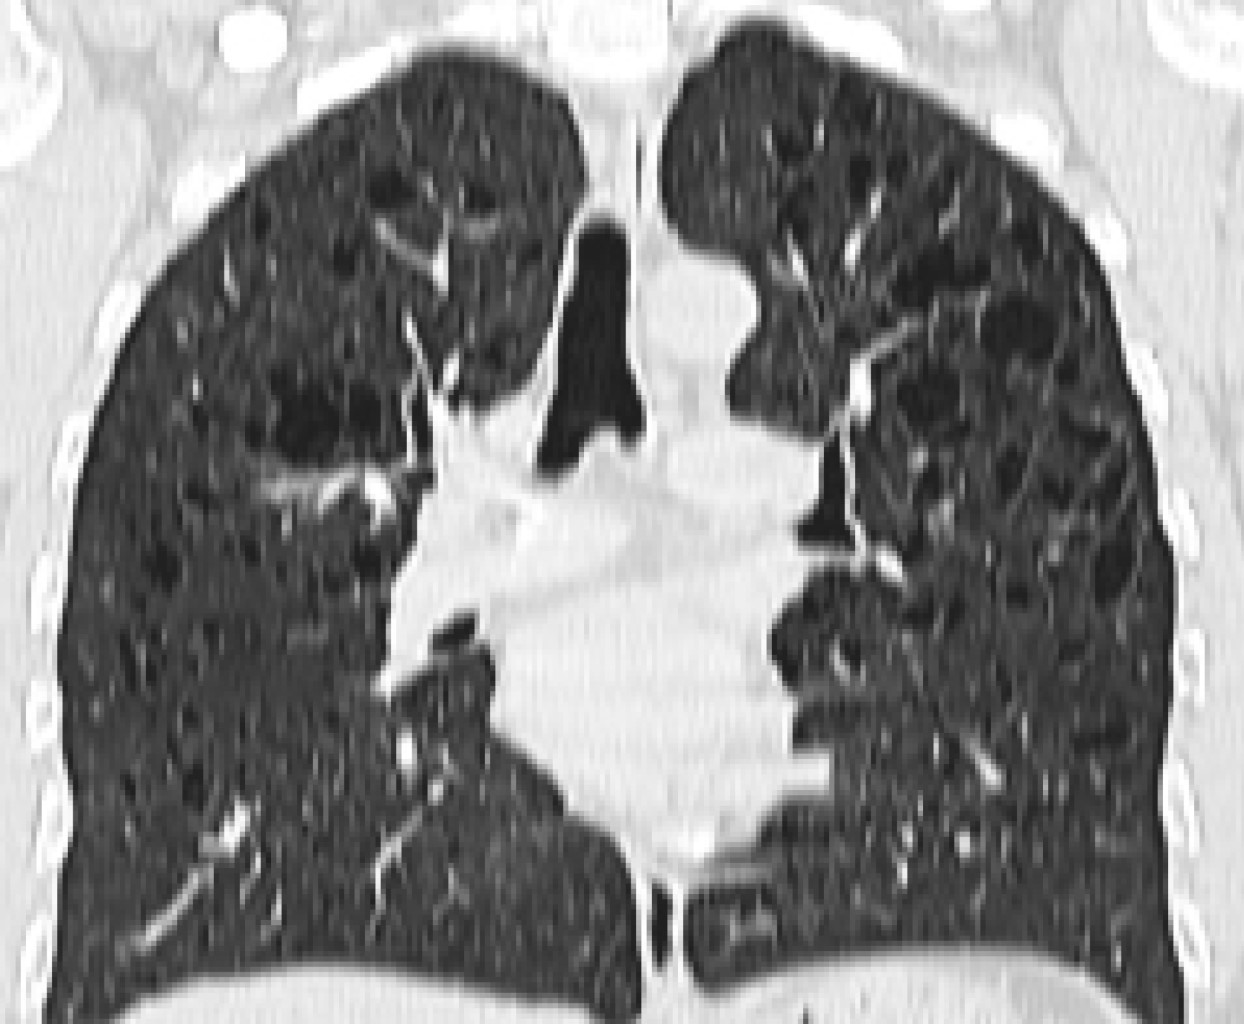

Se decidió realizar una tomografía computarizada (TC) para la valoración de otras posibles lesiones asociadas. El estudio puso de manifiesto de manera incidental la existencia de numerosas estructuras quísticas de paredes mal definidas con clara predominancia en ambos lóbulos superiores, asociando pequeños nódulos de distribución centrolobulillar. Los hallazgos radiológicos son sugestivos de enfermedad de histiocitosis de células de Langerhans pulmonar (Figuras 1 y 2).

La tomografía computarizada de alta resolución (TACAR) ha facilitado y proporcionado una mejor valoración del parénquima pulmonar. El patrón radiológico principal es la existencia de nódulos centrolobulillares de predominancia en lóbulos superiores y de tamaño inferior a 1 centímetro. La progresión de las lesiones quísticas en la TC se correlaciona con un mayor deterioro funcional pulmonar.6

Figura 2